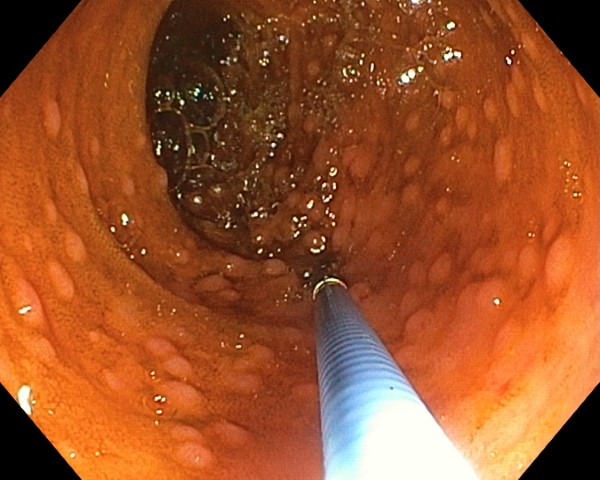

Potrivit unui comunicat de presă, de luni, al Spitalului Clinic CF Timişoara, dispozitivul are ataşată o cameră video HD prevăzută cu o lumină foarte puternică. Enteroscopul spiral motorizat este conectat la un turn endoscopic de ultimă generaţie care oferă vizualizarea de imagini la o calitate superioară (4K).

„Aparatul este prevăzut cu o spirală dintr-un plastic dur ce poate fi controlată electric cu ajutorul a două pedale, pentru înaintare şi pentru retragere, totul realizându-se cu sprijinul unui motoraş ataşat dispozitivului. Toate acestea sunt conectate la o unitate centrală. Mai mult, un controler permite oprirea automată a sistemului atunci când creşte rezistenţa la înaintare sau la retragere. Trebuie spus că enteroscopia este examenul endoscopic gold standard pentru diagnosticul, dar şi pentru tratamentul afecţiunilor la nivelul intestinului subţire. Mai mult, aparatul pe care îl folosim permite recoltarea de biopsii, obţinerea, practic, a unui fragment bioptic, ce este apoi analizat de histopatologi. În plus, se pot efectua diferite tehnici intervenţionale. De exemplu, oprirea unei hemoragii prin aplicarea de hemoclipsuri, coagularea cu argon plasmă sau excizia de polipi”, a declarat conf. dr. Christian Banciu, medic primar gastroenterologie şi medicină internă şi şef al Secţiei de Medicină Internă a Spitalului Clinic CF Timişoara.

„Aparatul pe care-l avem în cadrul Compartimentului de Gastroenterologie este primul şi, la ora actuală, singurul din România şi are mai multe avantaje. Pe de-o parte, reduce timpul de investigare, urmare a motorizării. Apoi, acel tub subţire, flexibil, poate pătrunde mai uşor în sistemul digestiv graţie spiralei, care îl ajută la înaintare, dar şi datorită insuflaţiei cu dioxid de carbon ce provine dintr-un dispozitiv special ataşat turnului endoscopic. Gazul reduce, în acelaşi timp, senzaţia de balonare, absorbindu-se mai uşor în intestin. Totodată, prin folosirea CO2, se limitează riscul complicaţiilor în cazul tratamentului leziunilor descoperite. Enteroscopia spirală motorizată poate fi efectuată retrograd, abord mai simplu, fiind asemănătoare cu o colonoscopie. Adică, aparatul este introdus în organism prin orificiul şi canalul anal. Investigaţia necesită o pregătire anterioară de o zi şi se face cu o sedare uşoară. Există însă şi abordarea anterogradă, cu anestezie generală, care impune prezenţa unui medic de terapie intensivă, aparatul fiind introdus prin gură”, a explicat medicul Christian Banciu.